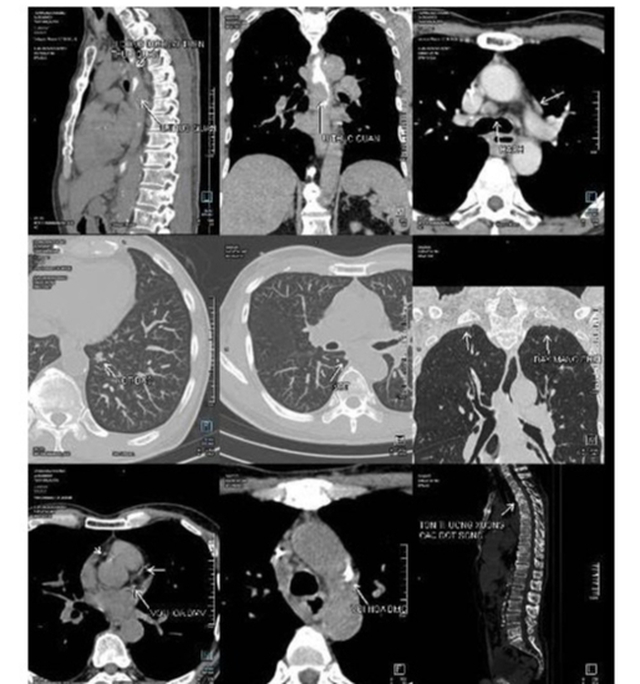

Cách đây 13 năm, ông mắc bệnh u lympho không Hodgkin, đã được điều trị khỏi ở một bệnh viện tại Singapore. Đầu năm nay, ông xuất hiện triệu chứng nuốt nghẹn, mệt mỏi, sút cân, đến BVĐK Tâm Anh Hà Nội thăm khám. Kết quả sinh thiết khẳng định ung thư thực quản, chụp PET/CT cho thấy bệnh giai đoạn muộn, xâm lấn rộng, di căn hạch và phổi hai bên.

Phim chụp PET/CT của bệnh nhân phát hiện ung thư thực quản lan rộng sang phổi. Ảnh: BVCC

6 tháng qua ông Hùng tuân thủ phác đồ điều trị của bác sĩ Sơn, hoàn thành đủ 6 đợt hóa trị. Kết quả chụp PET/CT cho thấy tổn thương thực quản giảm 80%, các vết di căn phổi giảm rõ. Bác sĩ Sơn đánh giá bệnh nhân đáp ứng tốt sau hóa trị, chuyển sang điều trị duy trì để nâng cao chất lượng sống.